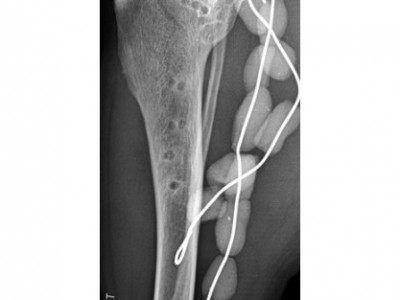

Suite au succès des dix premières éditions du Cours de Propédeutique et Sémiologie de l’Appareil locomoteur et des huit éditions du Cours de Pathologie articulaire de Bandol, le GECOV organise un Cours de Propédeutique, Sémiologie et Pathologie de l’Appareil locomoteur du mercredi 7 au samedi 10 juin 2017 à Bédoin, Salle municipale « L’Oustau d’Anaïs ». À la demande de nombreux participants des sessions précédentes, nous avons bâti cette année, un nouveau cours avancé avec deux focus : les pathologies ostéo-articulaires du jeune en croissance et la prévention et le traitement des infections ostéo-articulaires.

Etre capable de : renforcer les connaissances en pathologie ostéoarticulaire chez le chien et le chat.